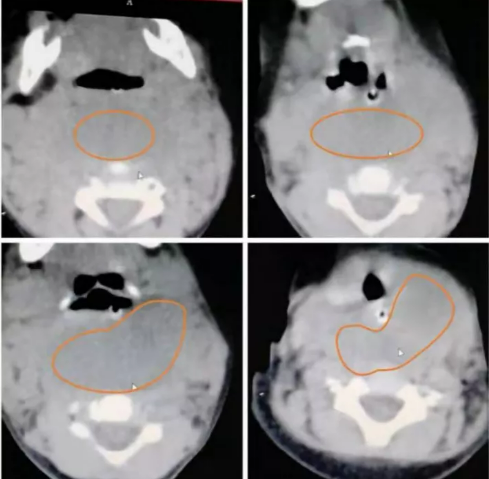

2021.12.28当地医院影像

2021.12.30治疗后影像